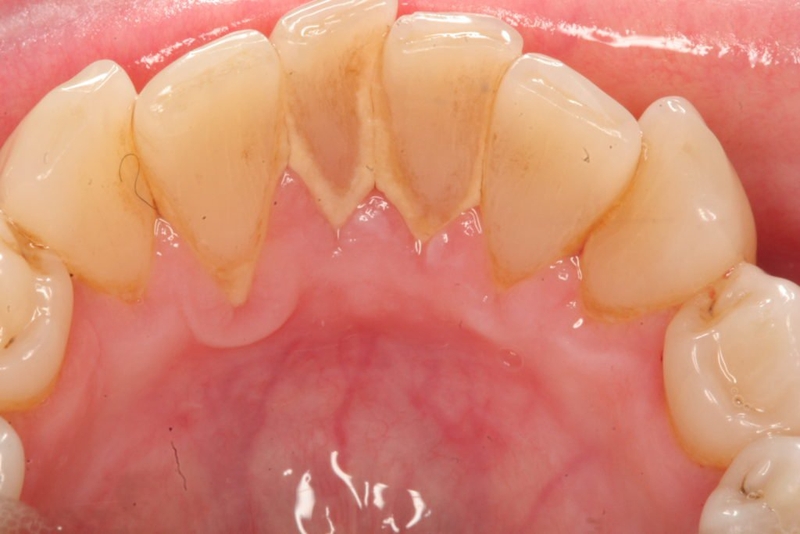

Cao răng (vôi răng) bản chất là sự kết hợp giữa muối canxi và phosphate, được hình thành từ các vụn thức ăn, muối trong nước bọt cùng với một số chất khoáng trong miệng, khi soi gương dễ dàng nhận diện qua những mảng bám màu vàng ố hoặc màu nâu đen tại vị trí chân răng.

Nhìn có vẻ vô hại nhưng thực tế lại là nguyên nhân gây mất thẩm mỹ, hình thành nhiều vi khuẩn làm hôi miệng, làm hư men răng và gây sâu răng, nguy hiểm hơn vi khuẩn sẽ gây kích thích và làm hại đến nướu răng dẫn đến các hiện tượng như:

Vi khuẩn còn là nguyên nhân dẫn đến nhiều bệnh nguy hiểm như viêm tủy, viêm niêm mạc miệng và lưỡi, viêm amidan,…